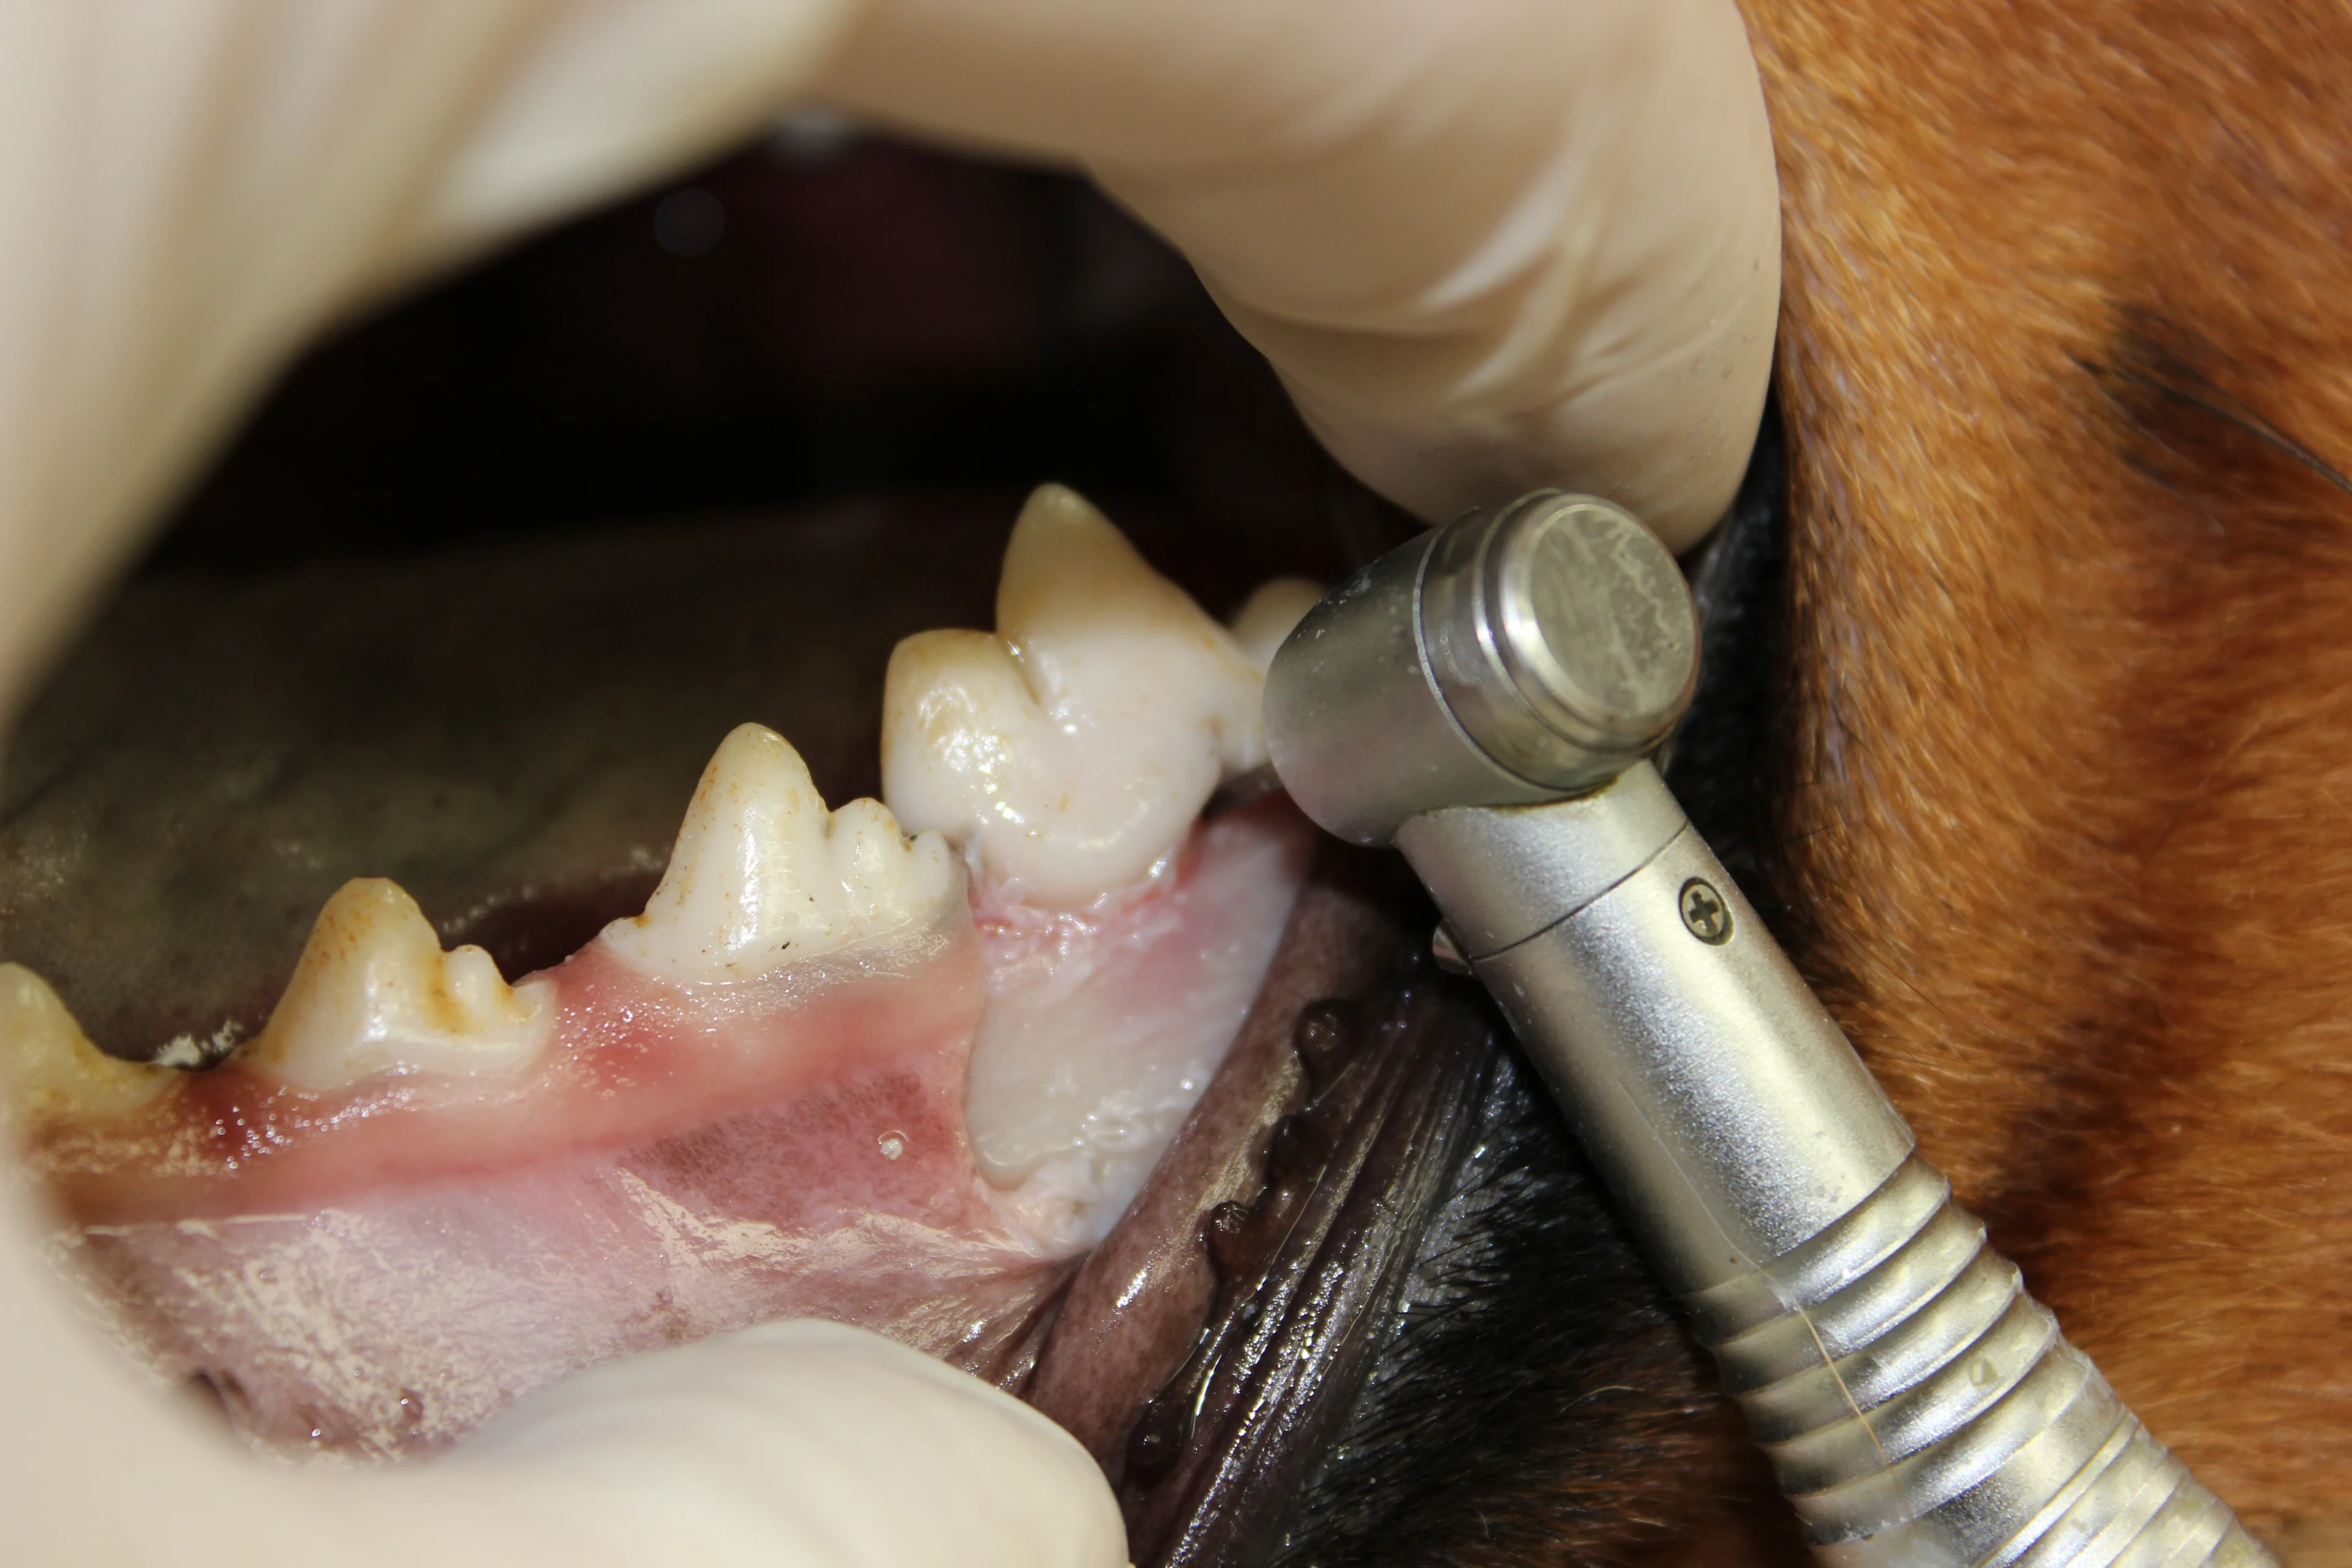

Slightly free the alveolar mucosa from the lingual surface of the extraction site with the periosteal elevator. Place the periosteal elevator between the mucosa and alveolar bone while using a #8 round bur in a water-cooled high-speed handpiece to smooth the sharp edges from the alveolar bone (alveoloplasty). Palpate to ensure no sharp edges remain.